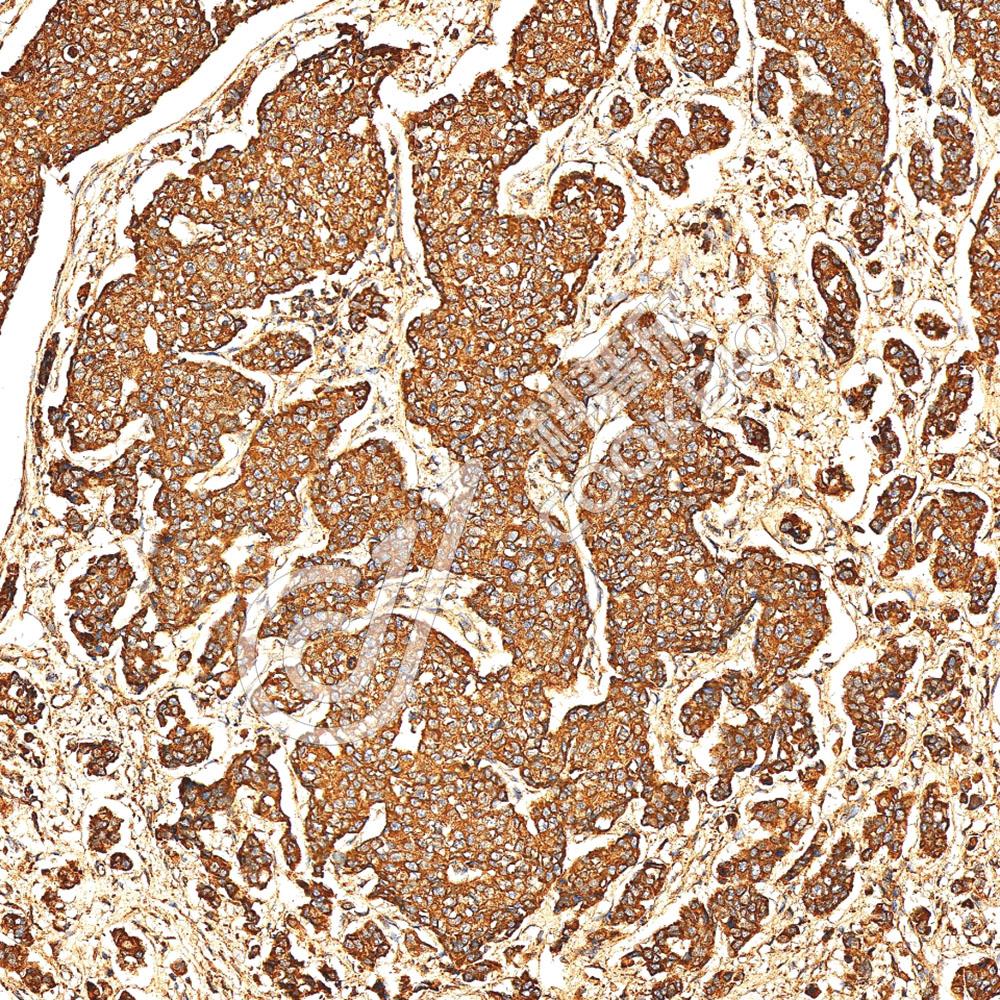

IHC检测E-cadherin蛋白(货号 K133246).

样品: 人食管, 4%多聚甲醛 (货号KSG1101) 固定12-24小时.

抗原修复: 柠檬酸抗原修复液(干粉, pH 6.0) (KSG1201), 98℃, 20分钟.

—抗: 1: 900稀释, 4℃ 孵育过夜.

二抗: S-vision免疫组化多聚二抗(山羊抗兔),即用型 (货号KB3906), 室温孵育20分钟.